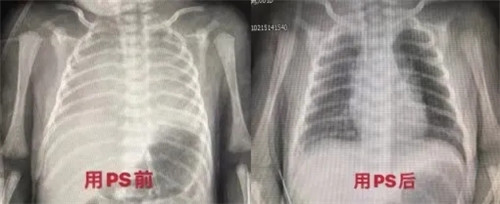

数分钟过去了,一个胎龄仅34+6周,出生体重2100g的小天使降临了。患儿因其母“胎膜早破”剖宫产娩出,在刘主任与助产士的护送下,迅速将患儿送入新生儿ICU病房。本以为这个小天使就这样平稳在暖箱中度过,怎料数分钟后患儿开始出现呻吟,口吐泡沫,呼吸困难明显,胸廓饱满,三凹征阳性,颜面发绀。刘静主任快速判断患儿病情后,要求高度警惕患儿存在新生儿呼吸窘迫综合征,快速联系放射科完成床旁胸片,并予CPAP辅助通气,缓解呼吸困难。季蓓护士长有序组织护士准备气管插管等抢救设备,随时待命。仅数分钟,床旁胸片完成,当看到胸部“白肺”的提示后,大家明白必须快速完成猪肺磷脂注射来促肺成熟,否则患儿呼吸困难只会进行性加重。

患儿病情刻不容缓,必须与时间赛跑。刘静主任立即与家属沟通病情,签署行气管插管有创操作以及PS(猪肺磷脂注射液)滴入知情同意书。云萍护士快速与急诊药房联系,很快完成PS取药。张鸾值班医生已经为患儿完成气管插管准备工作。在刘静主任的指导下,快、准、稳一次完成气管插管,立即进行PS气管内滴入。很快,患儿面色转红润,呼吸困难明显好转,无呻吟,三凹征阴性,大家都松了口气。